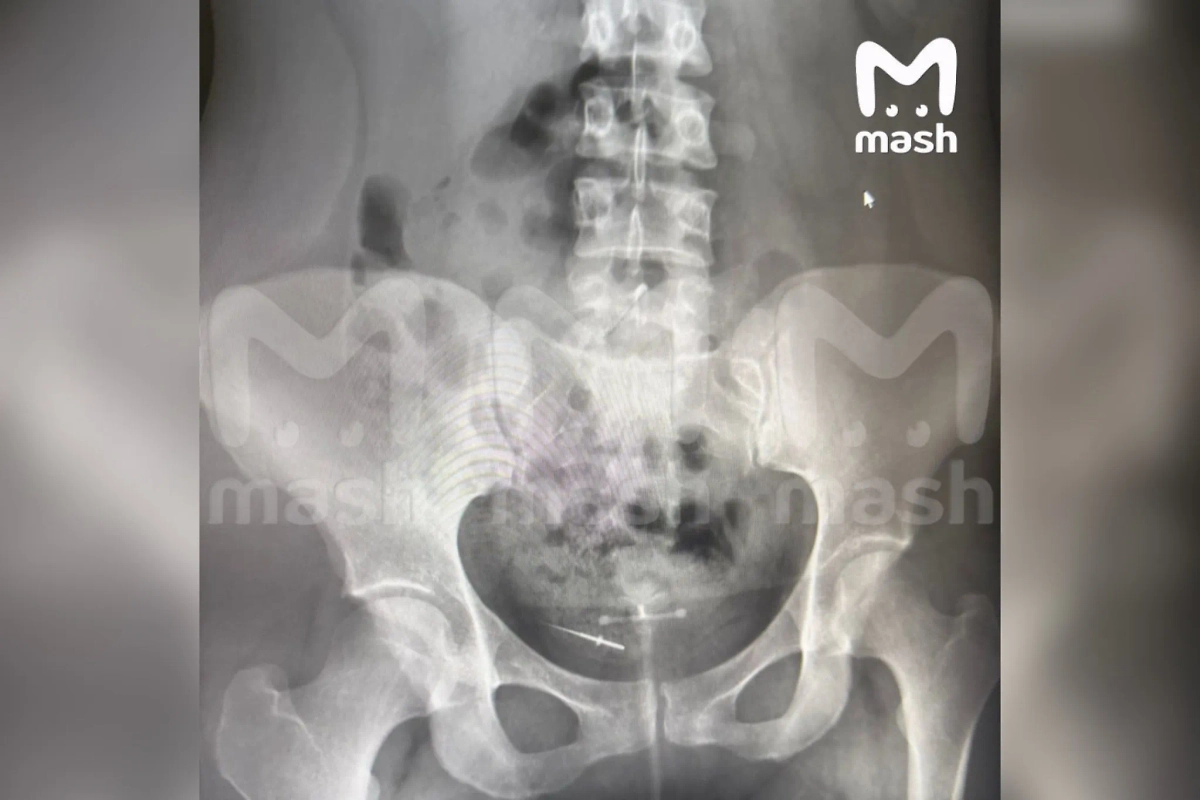

В кишечнике 26-летней жительницы Уфы нашли иглу после приёма у стоматолога. Как сообщает Telegram-канал Mash, девушка могла проглотить инструмент для обработки каналов.

Сразу после процедуры пациента почувствовала резкую боль в животе и сделала рентген. Оказалось, что в кишечнике находится инородный предмет — протейпер. Он успел мигрировать в нижнюю часть туловища. При этом стоматолог уверяет, что никакие инструменты не теряла.